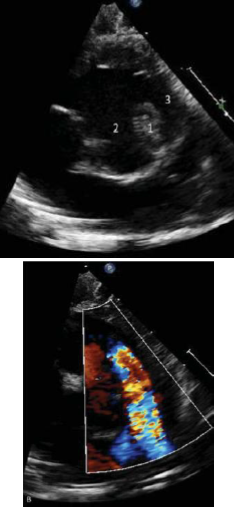

Com base na patologia ilustrada a seguir, qual defeito associado é mais comumente encontrado?

Sobre a patologia ilustrada na seguinte figura, é correto afirmar que